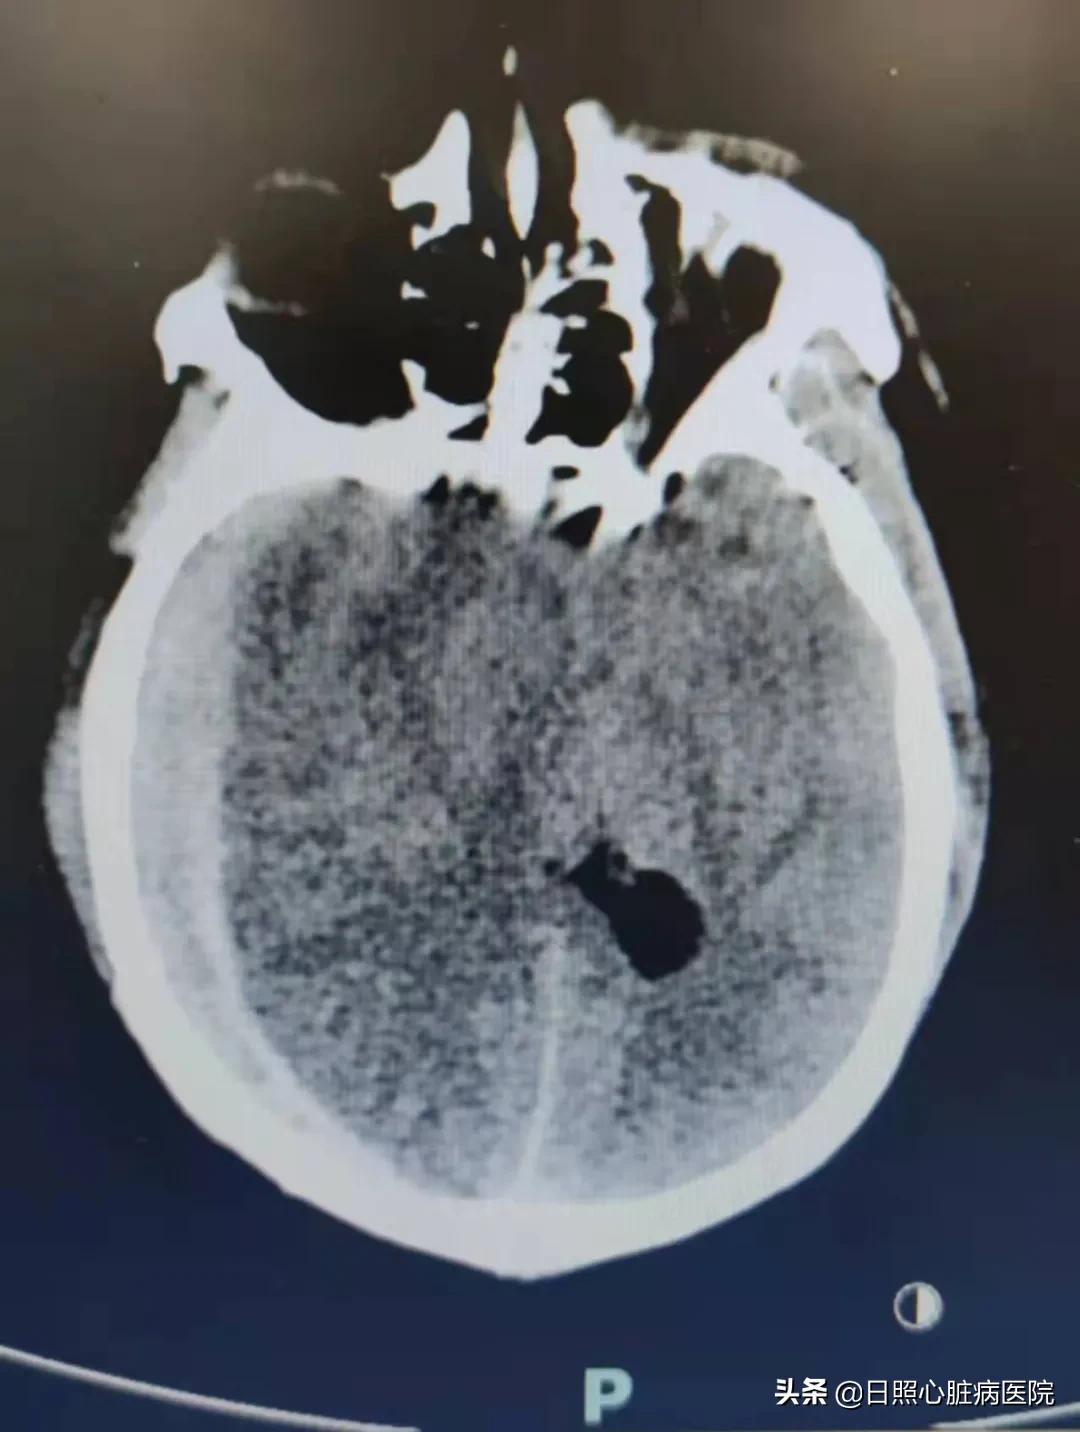

双侧脑疝、重度颅脑损伤、脑内血肿、创伤性蛛网膜下腔出血、多发性颅骨骨折……生死边缘,日照心脏病医院多学科协作,成功为37岁重型颅脑损伤合并双侧脑疝的曹先生紧急行双侧颅内血肿清除、去骨瓣减压手术,挽救了患者生命,目前,患者恢复良好,现已康复出院。

经影像检查提示曹先生的颅骨硬膜下存在血肿,脑科中心副主任医师厉宗祥意识到患者的病情在逐步加重,颅内血肿有向对侧发展的趋势,已经形成脑疝,随时会有生命危险,需要立即手术。

手术室中,无影灯下,脑科中心副主任医师厉宗祥手持柳叶刀,将颅内厚厚血肿一点点清除,同时移去骨瓣减轻颅内压力,可是,术中明显膨出的脑组织让他意识到,左侧血肿也在进一步增大。于是,立即在DSA机器的辅助下行颅脑CT检查,结果正如他所料,左侧脑疝已形成。

左侧血肿清除手术也在有条不紊地进行着,手术历经四个多小时顺利结束,整个手术过程患者出血约800毫升。

术后,曹先生被送往ICU,进行进一步治疗。复查CT显示,脑部血肿完全清除干净;术后第二天,曹先生意识清醒,能自动睁眼并遵医嘱活动肢体;在ICU医护人员的精心护理下,进行预防感染、预防压疮、预防下肢静脉血等治疗后,曹先生的生命体征平稳,转入脑科中心病房进行恢复期的治疗。